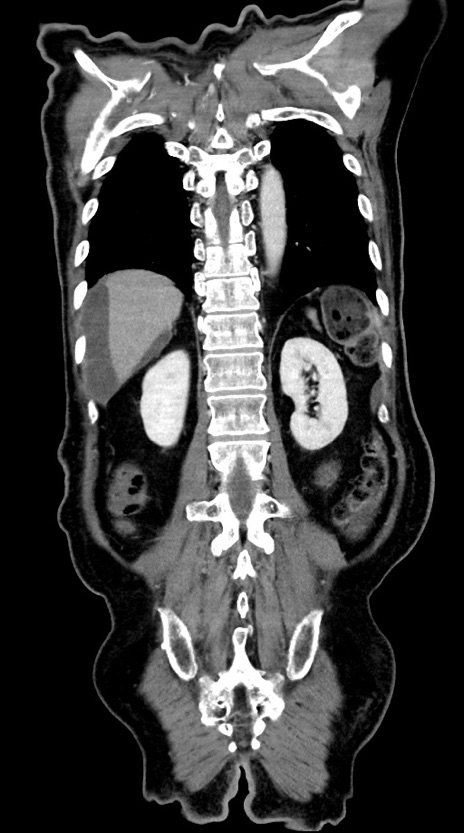

症例28(冠状断像)

【症例】60歳代男性

【主訴】嘔吐

【現病歴】胃癌にて胃全摘後。食思不振が悪化し、夜中に嘔吐することがある。

【既往歴】胃癌、胃全摘、脾摘、胆摘後

【データ】WBC 5900、CRP 10.56